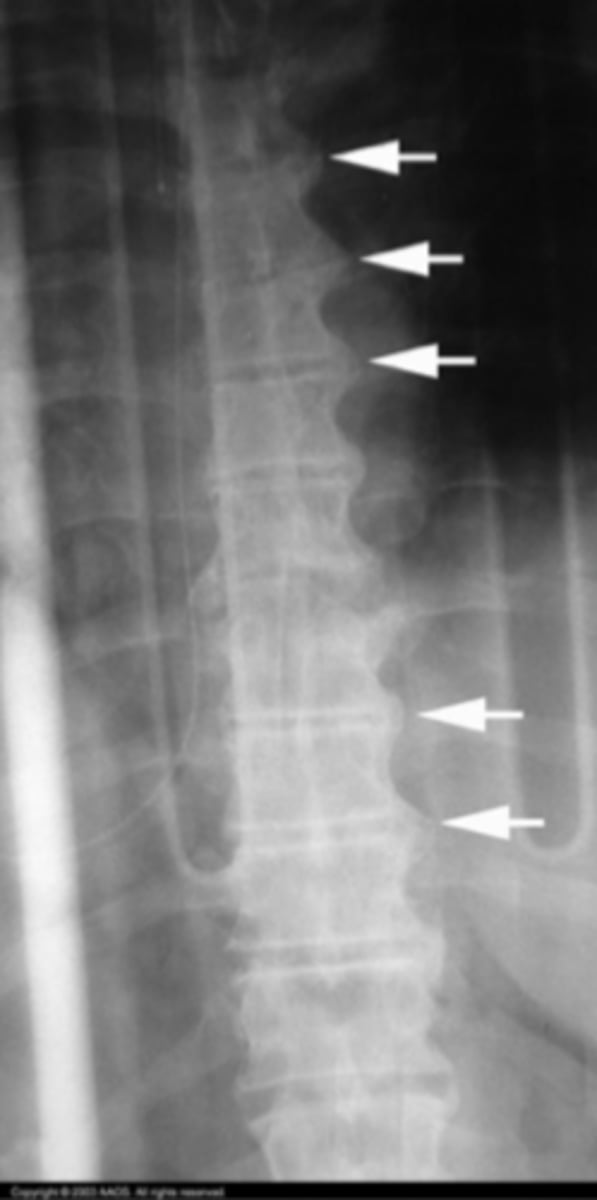

Bamboo spine of Tspine

What is the issue?

Tuberculosis of the Tspine